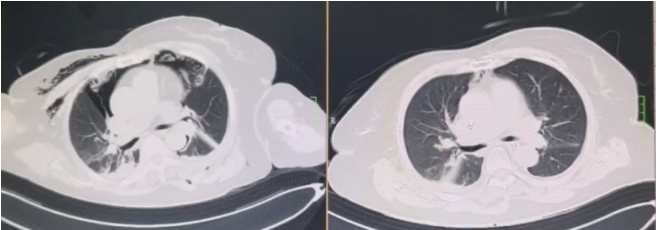

良性中心气道狭窄分为结构性和动力性(6种类型),结构性狭窄包括:管腔内生长(1型),外源性压迫(2型),瘢痕孪缩(3型),扭曲变形(4型);动力性狭窄包括:气道膜部向内膨出(5型),气道软化(6型)。对于动力性狭窄,应考虑用力呼气时的状态,通过操作者的判断,定出最合适、最接近的狭窄程度。治疗方法的制定不仅与气道狭窄程度和长度有关,还与是否存在狭窄过渡段有关。狭窄长度的计算应包括过渡区域。良性气道狭窄形态学分类的诊断方法应通过支气管镜所见及放射学检查来确定。每一个狭窄都可以用4个数字来表示,分别代表部位、类型、狭窄程度、狭窄长度。如:1344代表声门下瘢痕性挛缩性狭窄、狭窄程度>75%、狭窄长度>5 cm,这是一种非常难以处理的良性气道狭窄;2311代表气管瘢痕性蹼状网眼狭窄、狭窄程度<25%、狭窄长度<1 cm,这是一种比较容易处理的良性气道狭窄。热消融技术(APC、电凝、激光)是治疗增生性气道腔内病变(如良性肿瘤和单纯肉芽)的简单、快速的方法。但在治疗瘢痕狭窄病变时,其本身可对气道造成更重、更大范围的损伤,引起更为严重的肉芽组织增生和瘢痕形成,从而导致复发率高,且治疗次数的增加可导致狭窄病变范围增大并最终破坏软骨,导致气道塌陷,使患者彻底失去治愈的机会。电凝和APC仅适合管腔内生长的1型良性中心气道狭窄,并不适合其他类型良性中心气道狭窄的治疗。即便如此,基底部的处理也应避免使用此类治疗方法。针形电刀与气道黏膜接触面极小,不会造成损伤面扩大,瘢痕性气道狭窄的治疗宜选用针形电刀进行切割、松解。因激光也有切割的作用,因此也可选用激光治疗,钬激光、铥激光控制烧灼深度最浅可达0.4 mm,因此更适合良性瘢痕增生性气道狭窄的治疗。冷冻治疗分为冷冻切除(简称冻切,cryoextraction)及冷冻消融(简称冻融,cryoablation)。对于腔内生长的病变可采用冻切治疗,由于容易出血,其安全性不如热消融技术。对于瘢痕病变,冻切技术无法实施,则采用冻融治疗,冻融治疗不促进肉芽组织增生。与热消融相比,冷冻不易导致软骨损伤。通常在热消融治疗接近气道壁时或球囊扩张后采用冻融治疗处理剩余病变,有利于减轻瘢痕再狭窄发生的速度与程度。严重气道狭窄在开通气道前不要使用冻融,因其可引起气道水肿,加重气道狭窄,从而导致窒息。因此,冻融治疗后肺部体征监测及气管镜复查十分重要。机械扩张技术包括球囊扩张和硬质支气管镜扩张,并发症有气道撕裂、再狭窄、出血。(1)球囊扩张:是治疗瘢痕性气道狭窄最主要的技术,其优势是患者治疗后无明显的狭窄段延长,狭窄复发时再狭窄的程度比热消融治疗后轻得多,有利于维持气道复张的疗效。对气管黏膜损伤小,可以在软镜下应用,但需要中断通气。对于挛缩、韧性较强的瘢痕,可先用针形电刀进行切割以松解瘢痕;避免直接暴力球囊扩张,导致气道膜部的撕裂伤。(2)硬质支气管镜扩张:其优势是扩张时不需要中断通气,安全性更好。针对瘢痕肉芽组织增生导致介入治疗后的气道再狭窄,可采用气道狭窄部位局部应用药物的方法抑制瘢痕肉芽组织增生。介入治疗后气道再狭窄可选择的治疗药物有:糖皮质激素、丝裂霉素C、曲尼斯特、紫杉醇等。通过直接植入放射性物质(最常用铱-192)或经过可弯曲支气管镜近距离照射气道瘢痕肉芽组织,促使成纤维细胞凋亡。气道支架置入首选硅酮支架,禁用金属裸支架。支架治疗应作为良性气道狭窄最后选择的治疗技术,启动气道支架治疗的指征:①应用前述各种治疗方法疗效不佳,不能维持气道通畅;②在确定外科手术前临时放置;③外压性气道狭窄;④气道软化、塌陷且无法或不准备行外科手术治疗。病例1:17岁,女性,骨折术后肺炎插管,拔管后(2月14日)气道明显狭窄(图3)。2月15日评估:HR 113次/min,R 24次/min,静息下SpO2 97%(FiO2 50%),咳嗽及说话后喘鸣,有阵发性血氧下降。会诊后拟行急诊介入治疗。2月15日无痛气管镜示:声门下腔黄色及乳白色膜状坏死物,气管上段大量黄色坏死物并管腔重度阻塞,仅见小孔,以冷冻法清除坏死物后管腔通畅(图4)。术后气促明显改善,无需吸氧。病例2:77岁,女性,呼吸困难2个月,加重3天,于2023年12月2日入院(2023年9月气管插管,插管后20余天后拔管)。入院当天查体:HR 125次/min,R 30次/min,静息下SpO2 96%(高流量FiO2 30%),PaCO2 56 mmHg。患者术前影像如图5所示。12月3日查体:HR 140次/min,R 35次/min,BP 190/90 mmHg,SpO2 68%~75%(FiO2 100%),躁动不安,急查血气分析:PaCO2 89 mmHg。紧急床旁无创通气支持下气管镜:气管上段狭窄80%以上,较多黄白黏稠分泌物在狭窄口随呼吸摆动,予抽吸后SpO2升至98%,见狭窄处直径约3 mm,外径5.2 mm,软镜无法进入,遂置入导丝,10#球囊扩张多次,狭窄部位增宽,外径4 mm气管镜引导6.0号气管导管经口插管成功(图6)。插管后患者HR 98次/min,复查血气分析示PaCO2 41 mmHg,氧合指数300 mmHg以上。12月4日气管镜示:右鼻旁路进镜,缓慢退气管导管至声门,距声门3 cm处狭窄,直径7 mm,予12#球囊扩张1 min,2次,未见出血,扩张后直径约12 mm,地塞米松局部保留,气管导管复位(图7)。12月5日拔除气管导管。12月6日气管镜示:气管上段瘢痕狭窄(管径10~12 mm),少许膜状坏死、未见肉芽,予以清除坏死物,7点、11点冻融,术毕注入地塞米松5 mg(图8)。12月13日气管镜示:气管上段瘢痕狭窄(管径12 mm左右),少许膜状坏死、未见肉芽,予以清除坏死物,7点、11点冻融,术毕注入地塞米松5 mg(图9)。

12月8日复查胸部CT,气管管径较前明显增宽(图10)。患者于12月14日出院,于当地定期复查。病例3:80岁,男性,发现颈部肿块5年,咳嗽气促1个月入院(2024年1月6日)。2019年1月14日曾于外院置入气管硅酮支架。术前(1月6日):HR 95次/min,R 22次/min,静息下SpO2 97%(FiO2 29%),活动后喘鸣。1月8日硬镜示:气管上段膜部肉芽样新生物致管腔混合性重度狭窄(外压为主),冷冻+直钳清除气管上段膜部新生物(质韧,活检困难),术后直钳上调硅酮支架至气管起始部,完全覆盖狭窄处(图11),术后气促明显改善。术后病理:鳞状上皮化生,伴轻度非典型增生。1月12日凌晨1:09突发气促加重,喘鸣明显,HR 140次/min,BP 200/102 mmHg,R 35次/min,SpO2 97%(FiO2 35%)。紧急联系介入和麻醉团队进行急诊介入治疗,无痛喉罩下正压通气,患者喘鸣消失。支气管镜示:声门下腔水肿,气管起始部见大块坏死物堵塞管腔,随呼吸呈活瓣样,管腔明显狭窄,予冷冻+钳夹清理,支架未移位(图12)。

1月12日复查CT:支架位置良好(图13)。予无创通气与高流量交替,拟T管置入。1月14日患者夜间出现刺激性咳嗽,1月15日复查气管镜(软镜)示:声门下腔水肿并坏死物致管腔中度狭窄(图14),冷冻清理坏死物后见硅酮支架下移10 mm,支架第二次移位;声门及声门下腔注入地塞米松5 mg。硅酮支架难题就是肉芽增生和移位,与家属充分沟通后同意T管置入。1月17日全麻硬镜:声门下腔及气管起始部黏膜水肿并坏死物致管腔轻度狭窄,取出硅酮支架,置入T管(图15)。1月19日和20日两次复查气管镜:T管在位,管腔上缘少许坏死物(图16)。病例4:85岁,女性,反复气促2年,外院住院考虑气管外压性狭窄,支架置入失败,心跳骤停,困难插管后3月7日转入我科。入科:气管插管,HR 96次/min,BP 107/86 mmHg,R 24次/min,SpO2 98%(FiO2 100%)。腹膨隆明显。急查胸腹CT示腹腔、纵隔、胸壁及颈部多发积气(图17)。予腹腔穿刺排气。3月11日复查CT示积气明显减少(图18)。3月12日行全院大会诊,考虑结节性甲状腺肿可能,可考虑外科手术。下一步治疗面临难题:继续插管?还是支架置入后手术?与家属充分沟通后,家属拒绝再次支架置入,故继续插管并于3月15日于耳鼻喉科行甲状腺全切术+气管悬吊重建术。术后第3天(3月18日)拔除气管导管,3月28日顺利出院(图19)。因此,并非所有良性气道狭窄都需要介入治疗,解除原发病因最重要。